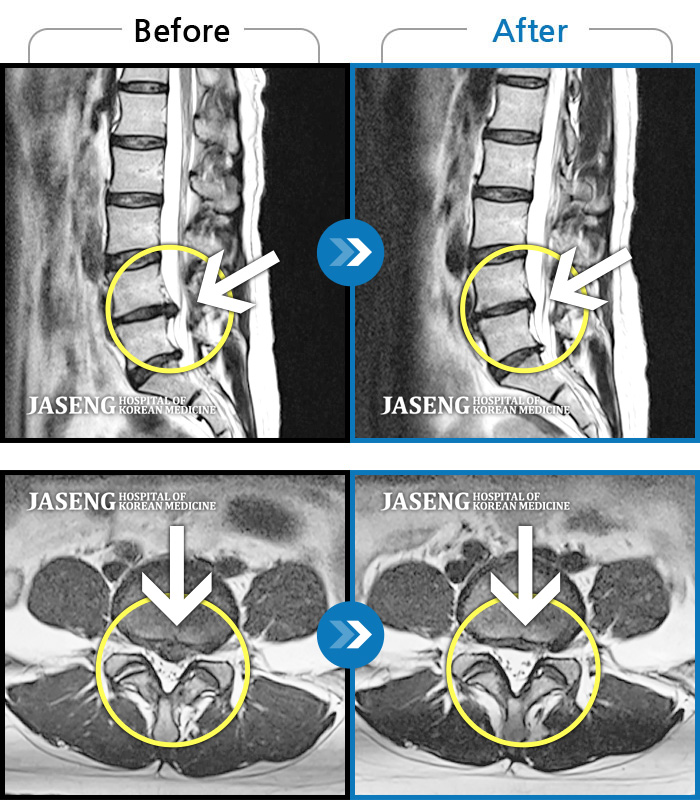

Before

After

환자에게 사전 동의를 받아 동일 조건에서 촬영되었습니다.

개인에 따라 치료 후 부작용이 발생할 수 있으니 의료진과 상담 후 치료를 진행하시기 바랍니다.

허리 골반 통증, 우측 다리에서 종아리까지 저리고 당김, 야간통

내원시 하부 요추 통증으로 보행 불가하고 야간통증